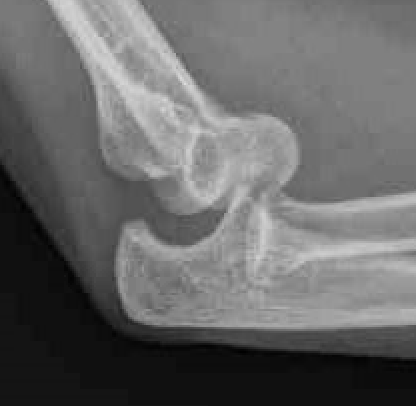

Bony Anatomy

| Ulnohumeral Joint | Radiocapitellar Joint | Distal Humerus |

|

Trochlea and ulna highly conformed - trochlea covered by cartilage in arc 300o - trochlea separated from the capitellum by groove - trochlea 6o valgus which creates carrying angle

Concave radial head - articulates with capitellum - posteromedial 2/3 articulates with sigmoid notch ulna - anterolateral 1/3 has no cartilage / safe zone |

Tilted anteriorly 30o in lateral plane - 5o internally in transverse plane - 6o of valgus in front plane |

Radial head important secondary stabiliser, especially when MCL deficient

Centre of rotation - trochlea - centre of rotation anterior to humeral shaft |